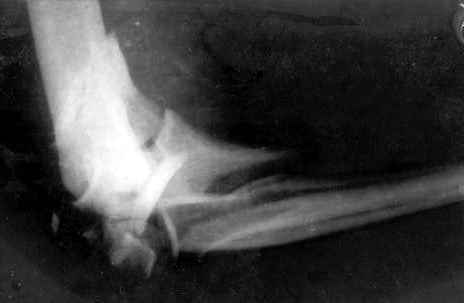

Здравствуйте, коллеги.Мужчина, 45 лет, ДТП 24.10.05. На сегодня неврологических расстройств правой кисти нет, отека нет, движения в правом плечевом и в правой кисти в полном объеме. Правый локтевой сустав сгибани 110*, разгибание 140*, наружняя ротация предплечья 45*, внутренняя 45*. Укорочение правого плеча 4 см. Больной просит у меня совет, стоит ли ему стремиться к эдопротезированию локтевого сустава.Я, к сожелению, не видел ни одного больного после эндопротезирования локтевого сустава.-- С уважением,Анатолий Борзунов